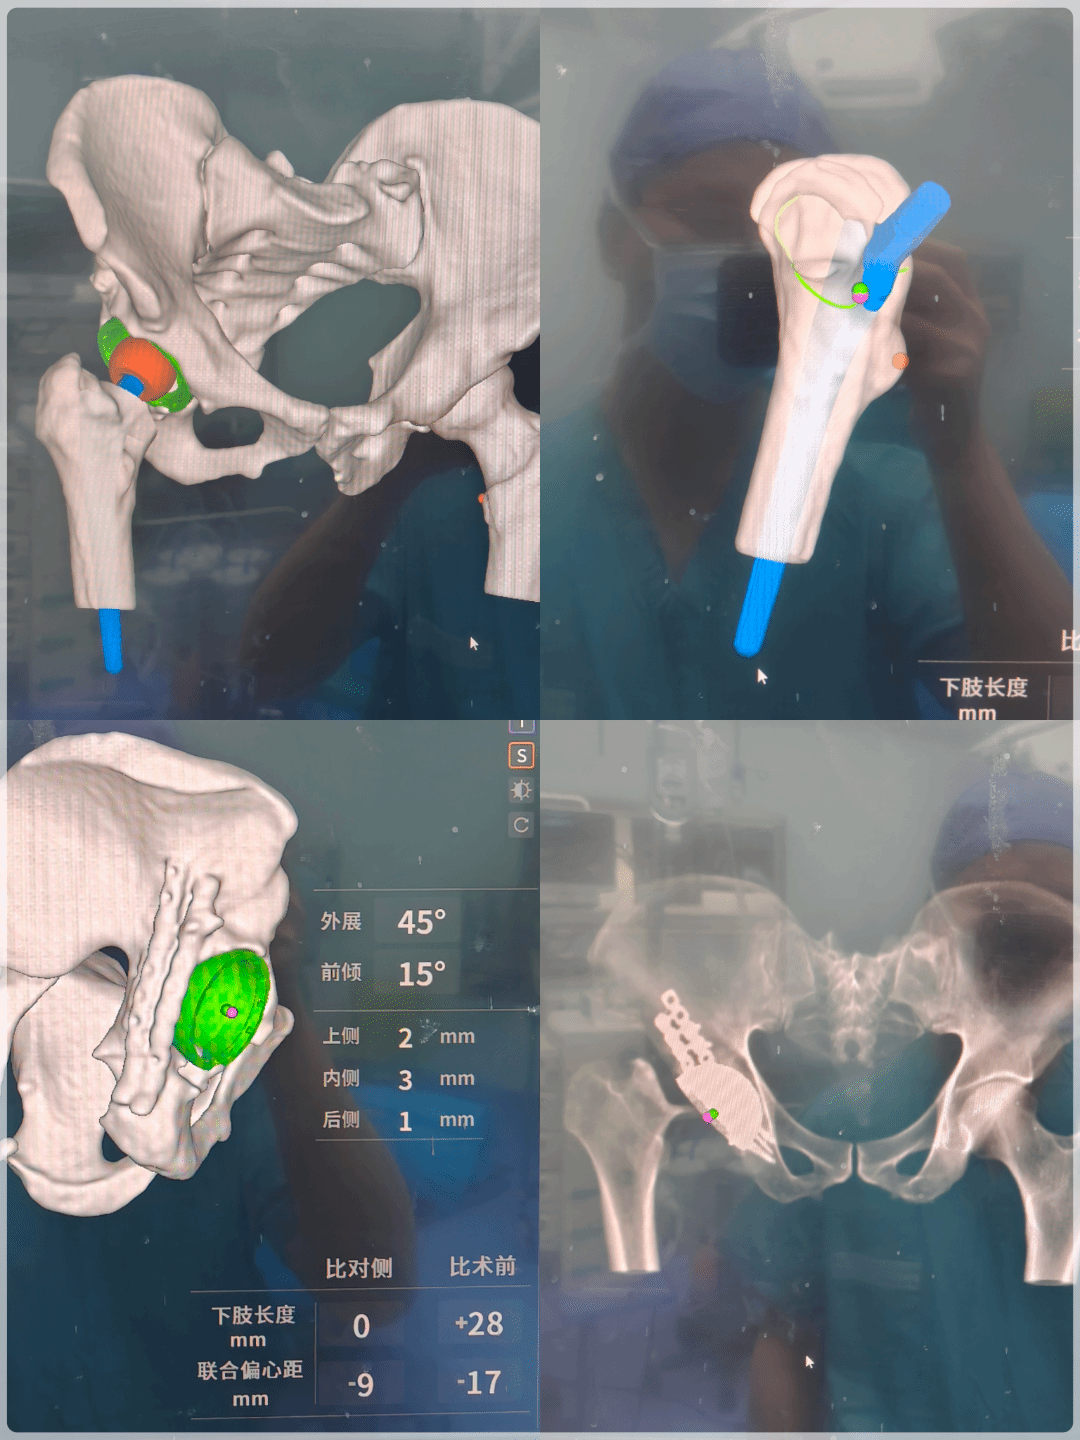

“机器人就像手术的‘智能导航’与‘精准机械手’,让复杂手术更可控、更精准、更安全。”郭旗主任介绍。术前,团队通过高分辨率CT为患者重建1:1三维数字模型,在智能规划平台上精准设计髋臼杯角度、股骨柄位置,个性化确定磨锉范围与假体型号,参数精确至毫米级。针对患者解剖变异,团队还模拟关节运动轨迹,提前规避撞击风险,制定出最安全的个体化方案。

(机器人实时动态定位)